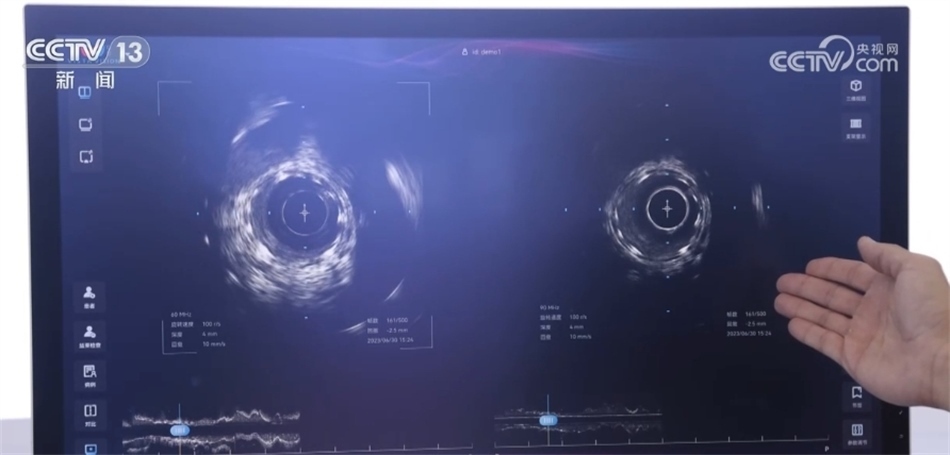

總臺(tái)央視記者 褚爾嘉:這里是一個(gè)傳統(tǒng)的血管的超聲圖像,我們可以看到血管的全貌。右邊這里是一個(gè)工作頻率高達(dá)100兆赫茲的超高頻的血管內(nèi)超聲圖像,通過(guò)技術(shù)升級(jí),現(xiàn)在我們可以更加清晰地看到冠狀動(dòng)脈的精細(xì)結(jié)構(gòu),這也是目前世界上清晰度最高的一個(gè)血管內(nèi)的超聲圖像。

中國(guó)科學(xué)院深圳先進(jìn)技術(shù)研究院研究員 馬騰:在醫(yī)學(xué)影像領(lǐng)域,圖像的分辨率和深度是不可兼得的。我們創(chuàng)新性地將一個(gè)超高頻的探頭和一個(gè)傳統(tǒng)的探頭融入到一個(gè)導(dǎo)管里,在不改變導(dǎo)管尺寸的情況下,可以為醫(yī)生提供一個(gè)大深度、高精度二者兼得的圖像。對(duì)于一些冠狀動(dòng)脈急性病癥,包括斑塊的診斷以及介入手術(shù)的治療,會(huì)給醫(yī)生提供一個(gè)更加全面、更加有效的醫(yī)療影像學(xué)工具。